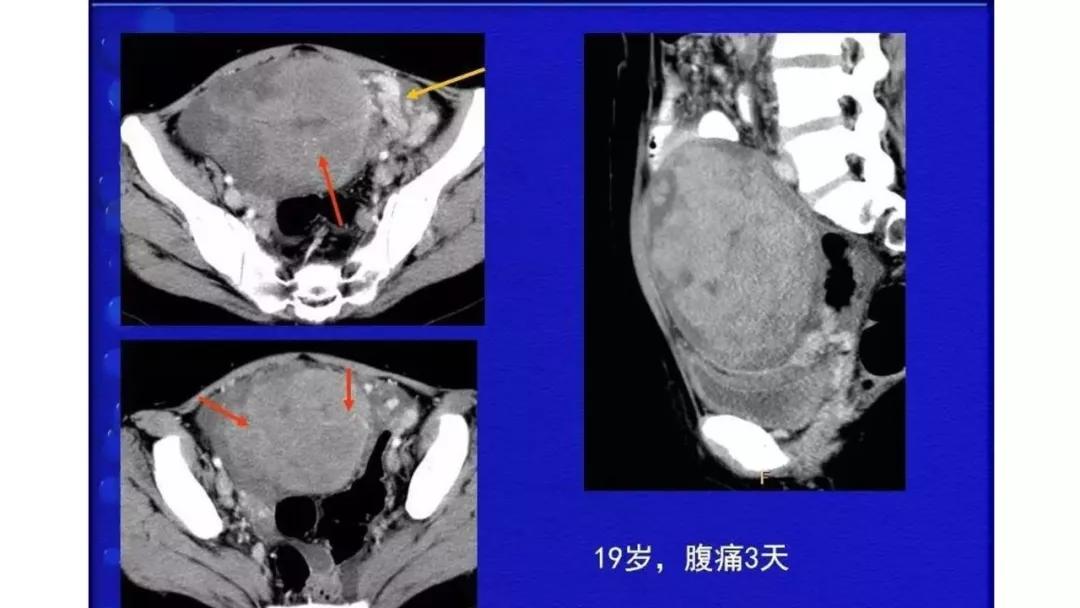

恶性者常呈实性或混杂性肿块,多数边界清楚,可伴有不规则沙粒状钙化。无性细胞瘤常为实性肿块,轻度强化,内胚窦瘤实性成分明显强化,不成熟畸胎瘤呈混杂密度。结合年龄及临床生化检查,有助于诊断。

- 纤维血管分隔呈分叶状:无性细胞瘤

AFP升高:卵黄囊瘤、无性细胞瘤、混合瘤

HCG升高:(首先要排除宫外孕)绒毛膜癌、无性细胞瘤